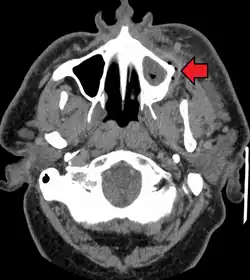

A dental infection resulting in an abscess and inflammation of the maxillary sinus